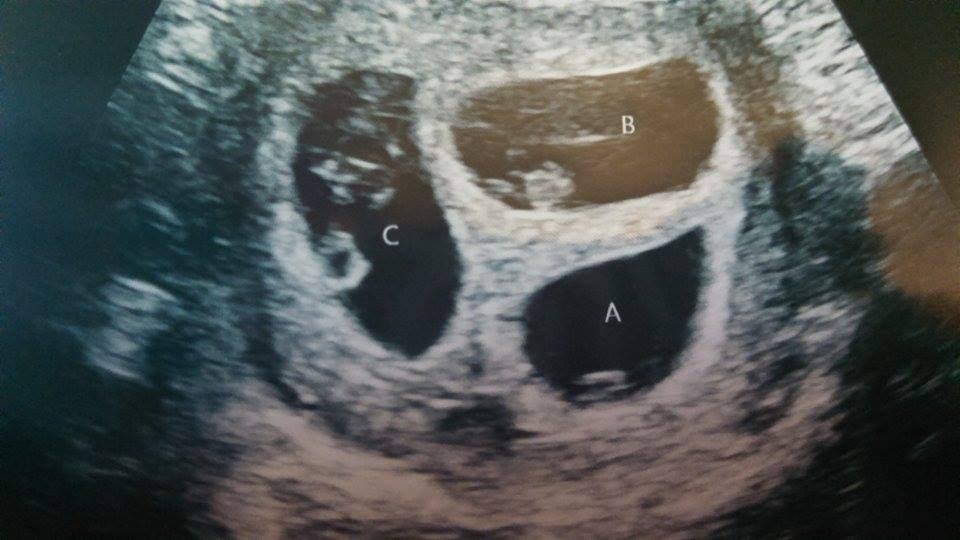

• We had our first ultrasound today at 7w5d after IVF with transfer of ONE embryo.  Imagine our surprise when we saw TWO babies! Identical twins - we are still in shock and yet so excited!  We saw both heartbeats, which was indescribably amazing.  We will have another US on 11/20 (8w6d) before graduating from our RE to our OB.

• @theatremandy - they didn't see a membrane but thought it might still be too early. I'll be getting another scan next week, so I guess we'll know by then! We are nervous but looking forward to the twin adventure! DW is an identical twin herself, so it'll be fun having another set in the family.